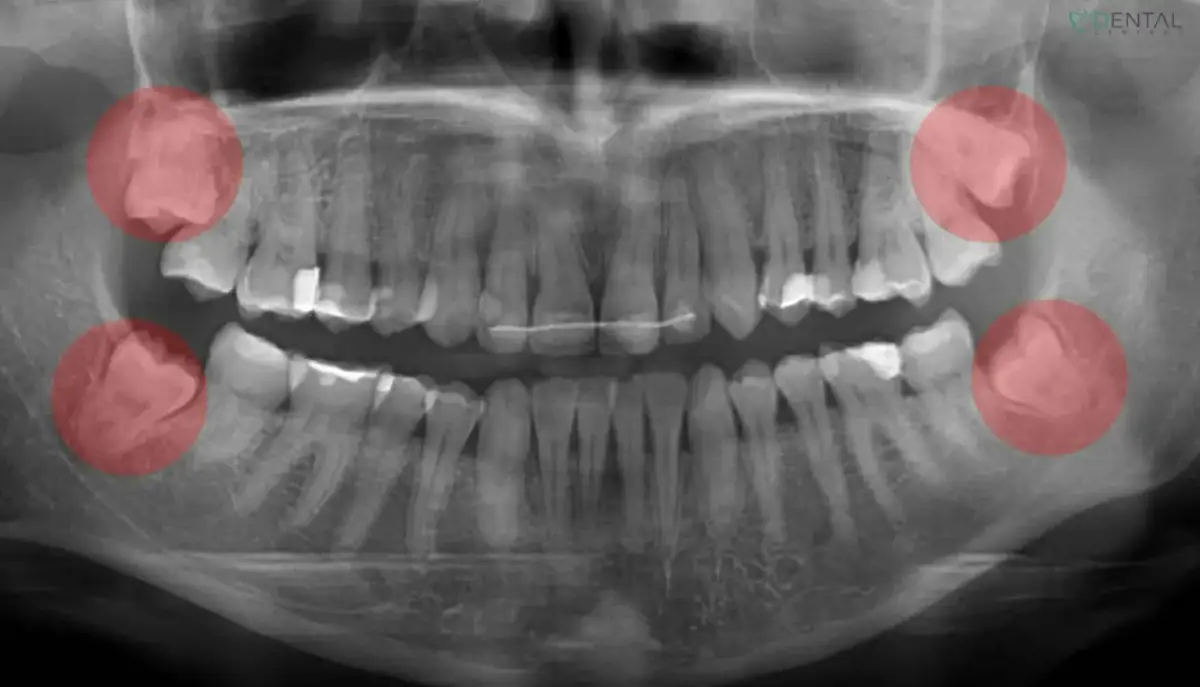

Zjawisko Godona: dlaczego ważna jest równowaga między górnymi i dolnymi zębami?

Zjawisko Godona to problem, który może wystąpić, gdy usuniemy tylko jeden ząb mądrości, nie usuwając jego odpowiednika w przeciwległym łuku (antagonisty). Na przykład, jeśli usuniemy dolną ósemkę, a górna pozostanie, ząb górny, pozbawiony kontaktu z dolnym, zacznie się wysuwać z kości (ekstruzja). To zaburza równowagę zgryzową, prowadzi do nieprawidłowych kontaktów podczas żucia, może powodować przeciążenia, a nawet problemy ze stawem skroniowo-żuchwowym. Dlatego często zaleca się usunięcie obu zębów mądrości z danej strony, aby zapobiec temu zjawisku i utrzymać prawidłową równowagę w zgryzie.